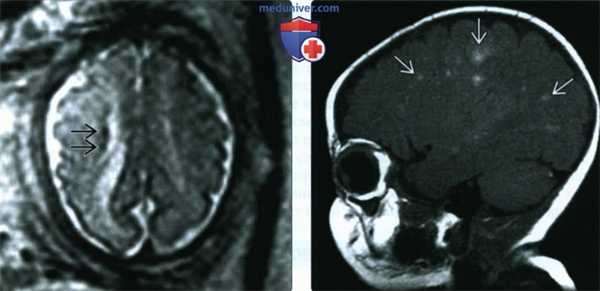

(Слева) МРТ плода с подозрением на туберозный склероз, Т2 HASTE, поперечная плоскость. Определяются гипоинтенсивные субэпендимальные узелки. При МРТ новорожденного были обнаружены дополнительные узелки, которые определялись у плода.

(Справа) МРТ ребенка в возрасте 2 мес., Т1-ВИ, сагиттальная плоскость. Визуализируется несколько гиперинтенсивных кортикальных туберсов, что является характерной находкой при туберозном склерозе. У всех плодов с рабдомиомой необходимо исключать туберозный склероз.